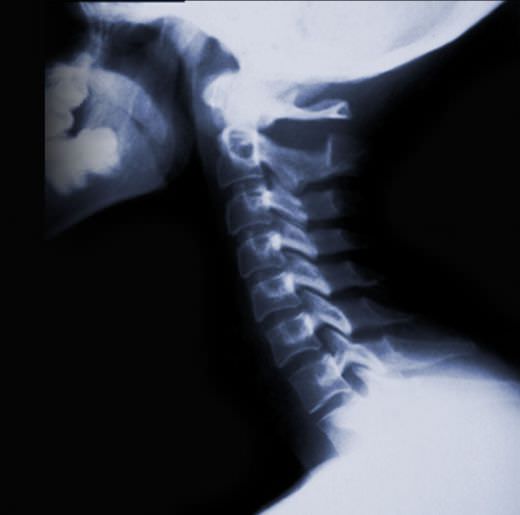

month, and what he found was, unfortunately, not good. My neck is

apparently curved the wrong way! I had no idea what a big problem this

could be. I’ve gotten a couple of other opinions from chiropractor

friends and they all agree that this does not need to go untreated.

Apparently it can cause a whole list of health problems now (like the

painful muscle spasms I’ve been struggling with the past year, and

problems like bronchitis, headaches, and a weak immune system, which I

struggled with most of my life) and if left untreated can cause bad

arthritis and degeneration as I get older. I’m SO thankful they were

able to find it now, when it can still be corrected! Please pray for

HEALING first and foremost, wisdom for my doctor, and that my body

will cooperate with the treatment.